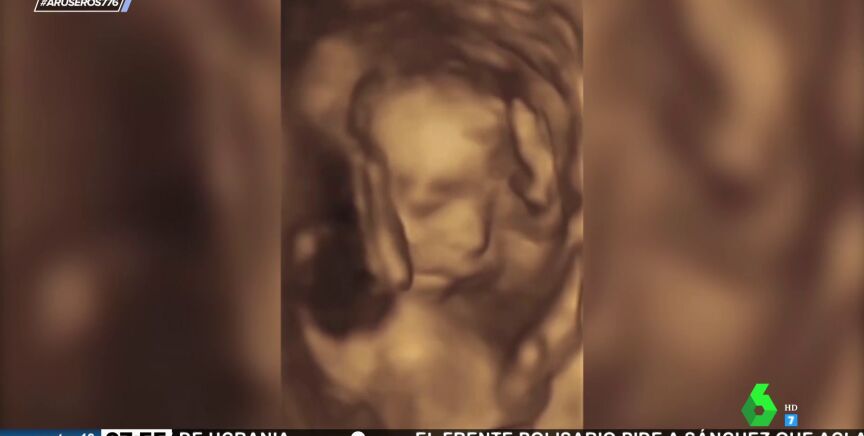

Aruser@s ha mostrado un sorprendente vídeo de una ecografía que ha compartido una madre de Pensilvania.

Las ecografías son un procedimiento rutinario al que las madres embarazadas deben someterse para comprobar el estado de su bebé. En ocasiones, los pequeños pueden moverse dentro del vientre de la madre, pero lo que se ha visto hoy en Aruser@s es del todo inusual.

En el vídeo que acompaña a la noticia, grabado por una madre de Pensilvania. se muestra una ecografía grabada en la que el bebé hace un claro gesto con la mano. "Se ha visto claramente que el bebé está haciendo una peineta", ha comentado Alfonso Arús. Por si no fuera suficiente, también ha hecho otro gesto más que ha sorprendido a los colaboradores de Aruser@s.